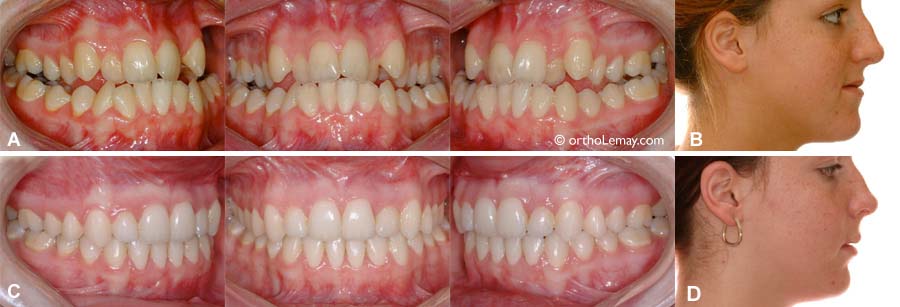

(A) Sévère malocclusion de type Classe III avec constriction maxillaire, occlusion croisée et béance postérieure bilatérales et manque d’espace important. (B) La déficience maxillaire (constriction et recul du maxillaire supérieur) se reflète dans le recul de la lèvre supérieure. (C) Occlusion à la fin du traitement. Un avancement maxillaire chirurgical fut nécessaire pour avancer la mâchoire supérieure et améliorer le profil. Aucune extraction ne fut nécessaire et aucun appareil d’expansion ne fut utilisé. (D) Le résultat final montre une lèvre supérieure plus avancée et un profil plus équilibré.